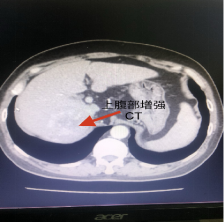

增强ct可见肝右叶占位病变

此次来院检查腹部增强CT提示:肝右叶占位性病变,考虑为原发性巨块肝癌,肿瘤大小达到60mmx84mm。患者之前已进行过结肠癌根治性右半结肠切除+胆囊切除术,病情复杂,身体虚弱,患者及家属强烈要求行微创介入治疗。经术前充分沟通及告知各种治疗方案的优缺点后,介入团队选择为患者行TACE介入微创治疗,后续将与靶向、免疫联合治疗达到肝癌的综合治疗。经过积极术前准备,普外科介入团队成功为患者实施了首例肝动脉化疗栓塞术,手术过程顺利,术后患者恢复良好,正在医院接受后续治疗。